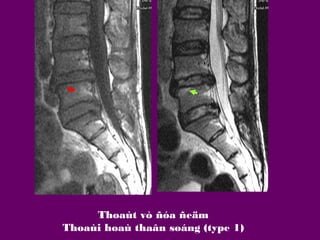

THOAÙI HOAÙ THAÂN SOÁNG

Phaân loaïi Modis

Loaïi 1:

phuø

Loaïi 2:

hoaù môõ

Loaïi 3:

hoaù xô

Vieâm,

Thoaùi

Thoaùt vò ñóa ñeäm

Thoaùi hoaù thaân soáng (type 1)

Thoaùi hoaù thaân soáng (type 2,3 )